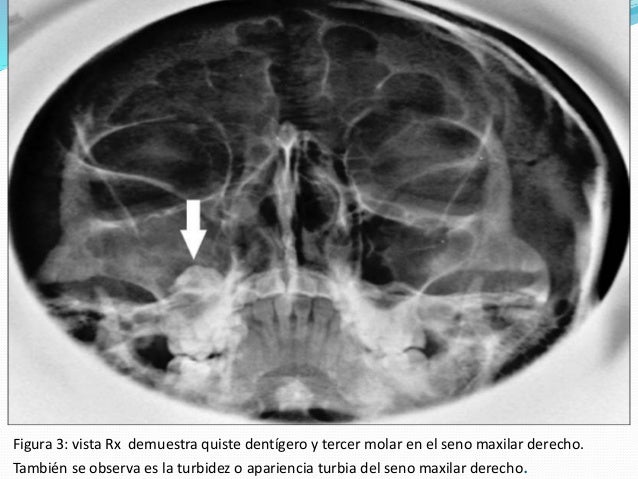

Rx. mentonasoplaca (Waters)

QUISTES

Subtopic